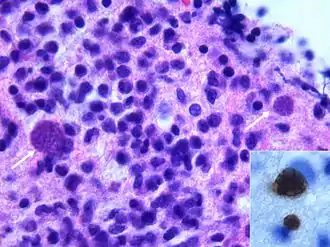

- le stade tachyzoïte, forme proliférative infectieuse chez l’hôte intermédiaire, se développe dans des vacuoles transitoires qui peuvent contenir jusqu’à 128 parasites ; cette forme peut se retrouver aussi chez le fœtus.

- le stade bradyzoïte, chez l’hôte intermédiaire, est contenu dans des kystes intracellulaires qui mesurent environ 100 µm de diamètre et contiennent plusieurs milliers de parasites ;

- Il se reproduit rapidement par un processus de multiplication asexuée (endodyogénie) chez l’hôte intermédiaire, toujours dans des macrophages. Puis il en sort en perforant la paroi au moyen d’une protéine qu’il produit (perforine). Des parasites génétiquement modifiés pour ne pas produire cette protéine ne peuvent sortir du macrophage qui gonfle en formant une boule[17]. Visuellement, l’enveloppe du parasite a la forme d’une goutte d’eau un peu arquée (toxon en grec signifie « arc »), d’environ 6 à 8 μm de longueur et de 3 à 4 μm de largeur. Le pôle postérieur arrondi contient le noyau tandis que le pôle antérieur plus aigu possède des ultrastructures adaptées à la pénétration cellulaire (complexe apical).

- Cette forme est plus résistante que la précédente (forme de résistance et de dissémination), entourée par une membrane épaisse, de forme sphérique ou ovoïde, elle mesure de 50 à 200 µm. Elle contient en plusieurs milliers d’exemplaires une forme végétative particulière le bradyzoïte ou cystozoïte (3 à 4 microns), un kyste de 100 µm en contient 2 000 à 3 000. Les bradyzoïtes résultent d’une série de multiplications asexuées, colonisant l’intérieur d’une cellule hôte. Leur multiplication est assez lente, et ne peut se faire que dans une cellule nerveuse ou musculaire de l’hôte intermédiaire. Dans les tissus, les kystes restent longtemps vivants, produisant des antigènes qui entretiennent l’immunité. Les kystes peuvent survivre plusieurs jours à température ambiante et plusieurs mois à 4 °C. Ils sont détruits par la chaleur (un quart d’heure à 56 °C) ou la congélation (24 heures à −20 °C)[18].

- L’oocyste coccidien est très résistant, même à l’eau de Javel (forme de résistance et de dissémination), c’est la forme que l’on retrouve dans le milieu extérieur (sol, plantes…) où il effectue sa maturation en quelques jours (de un à cinq) à température ambiante et en présence d’oxygène. Sa résistance lui permet de rester vivant pendant plusieurs mois dans le sol, mais il est détruit par la chaleur lors de la cuisson, la dessiccation ou la congélation (−30 °C). Il est le résultat de la reproduction sexuée du parasite chez le chat. C’est un ovoïde de 15 µm par 10 µm regroupant 2 sporocystes de 6 à 8 µm de diamètre, contenant 4 sporozoïtes chacun (un sporozoïte ressemble à un tachyzoïte).